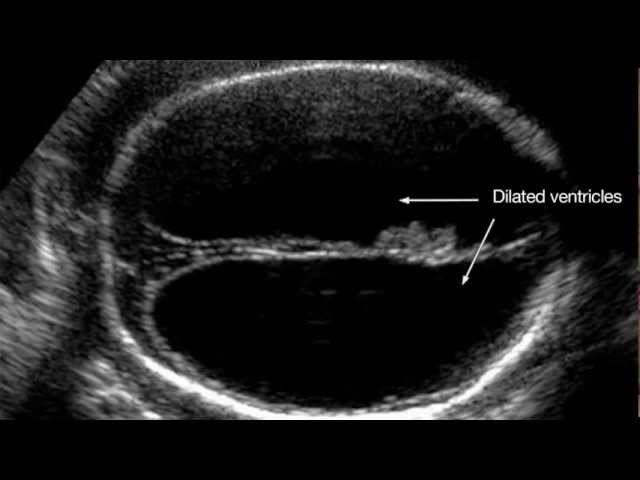

Hypoxia reduced oxygen tension asphyxia hypoxia rise of co2 acidosis asphyxia accumulation of. What to expect from a fetal well being pregnancy scan the sonographer will put some ultrasound gel on your abdomen and move a scan transducer over your skin. Ultrasound observation reveals the presence of diaphragmatic and chest wall excursion often best visualized at the level of the diaphragm figure 13 3a b. Assessment of fetal well being with ultrasound the practice of medicine is undergoing marked changes fueled by the infusion of vast amounts of new information concerning the etiology the progressive pathophysiology and the complexity of host response to disease states. Acid metabolite products of anaerobic. A minimum of 30 seconds of continuous fetal breathing is required.